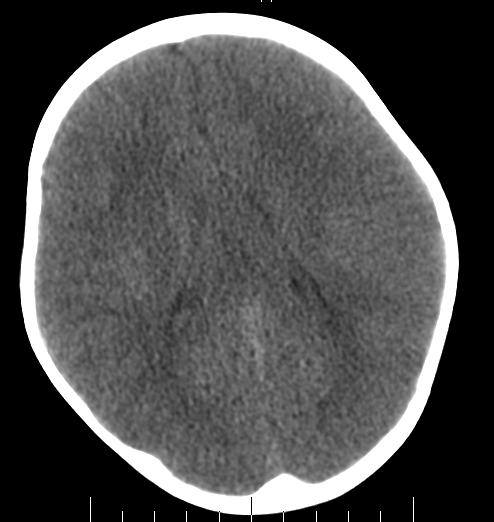

女,3岁,头部外伤一小时。半卵圆中心低密度是什么意思,病灶?侧脑室?请指教。

正常表现

幼儿正常脑白质表现,长期观察,必要时mr

不是侧脑室,考虑正常脑白质。为慎重,建议mr!